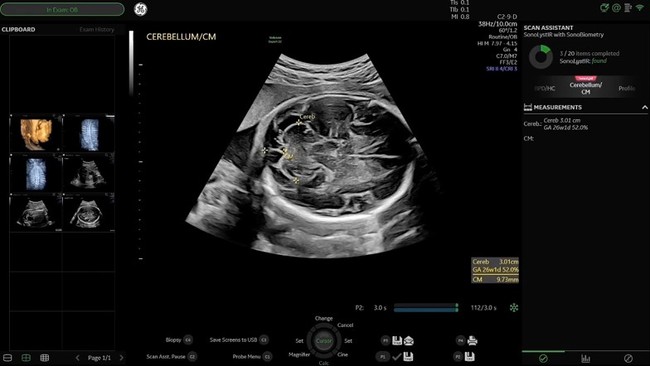

妊娠中期ISUOG(国際産婦人科超音波学会)ガイドラインに準拠したプロトコルであるSonoLystを搭載した。ユーザがフリーズした断面を,ガイドラインの基準断面に則したどの部位であるか装置が自動認識しユーザに提案し,ユーザがそれを受け入れると,チェック済項目として保存される。これにより,胎児スクリーニング検査のワークフロー改善とともに,取得画像のクオリティ担保や,自己学習の推進に貢献する。